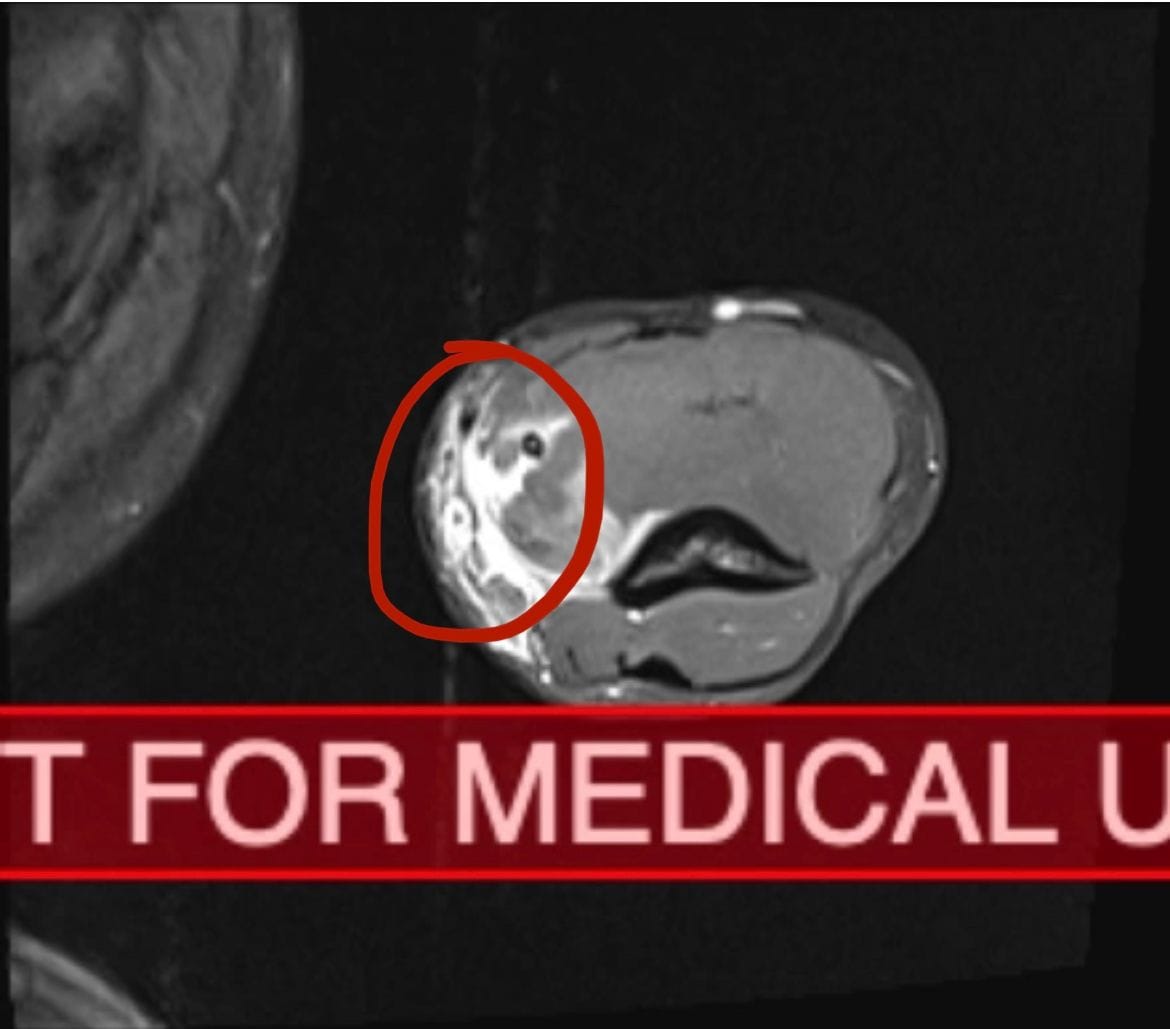

I realized I couldn’t. And for the first time in my life, I felt fear. The classic concussion symptoms settled in. I was stunned, confused, dizzy, and my head was killing me. Sound and light hurt. I wanted to go to sleep and never wake up. Within 24 hours, my bicep started swelling. Again my world came crashing down around me as I started to prepare myself for what all symptoms pointed to: a torn bicep. Eight to ten months of rest, and potential loss of some ability. I paid cash for a same-day MRI. As someone who is severely claustrophobic, laying in an MRI machine like salt in the wound.More fear.

Despite my physical symptoms, my MRI showed that although the swelling and fluid had camped out in my bicep, the muscle itself was intact. I was looking at just that tear in my brachialis. I had a dislocated rib that was pushing on my spine, which explained why I couldn’t get comfortable sitting, standing, or laying down. And they said that if my trap muscles hadn’t been as big as they are, I would have broken my neck.